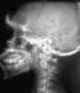

Cervical spine fracture

A cervical fracture, commonly called a broken neck, is a fracture of any of the seven cervical vertebrae in the neck. Examples of common causes in humans are traffic collisions and diving into shallow water. [Source: Wikipedia ]